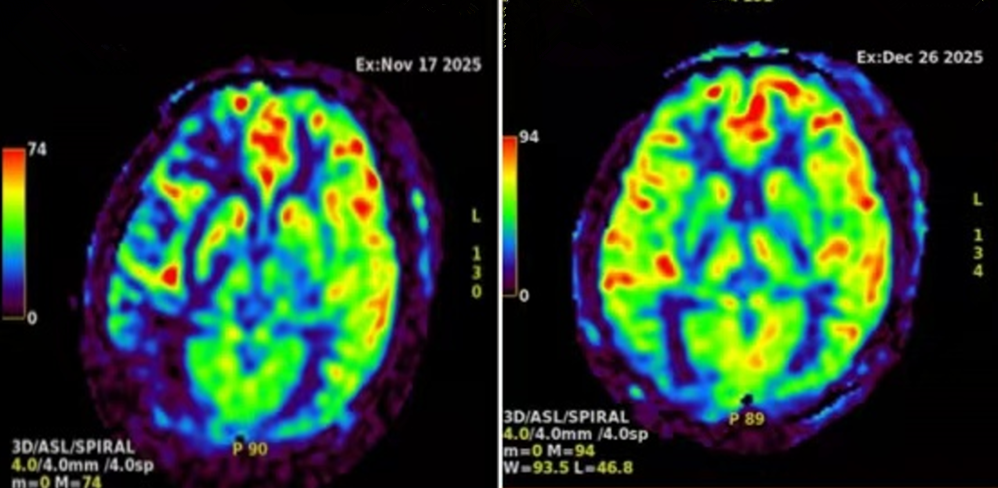

入院后,通过颈部血管增强磁共振、颅脑灌注磁共振等检查,明确患者近两月内出现颈内动脉闭塞残端综合征,这是导致脑部供血不足、反复发生缺血事件的重要原因。于天霞主任医师带领的神经内二科团队与柳海华副主任医师带领的介入小组经过术前讨论,认为血管闭塞在3个月内,仍有相应血管的卒中发作且有明显脑灌注不足的个体,应积极尝试慢病再通治疗。团队讨论制定了周密的个体化手术方案,完善术前预案与围手术期管理,在充分告知风险及获益的情况下,取得患者及家属同意后,决定实施颈内动脉闭塞开通术。

术前与术后1月颅脑灌注比较